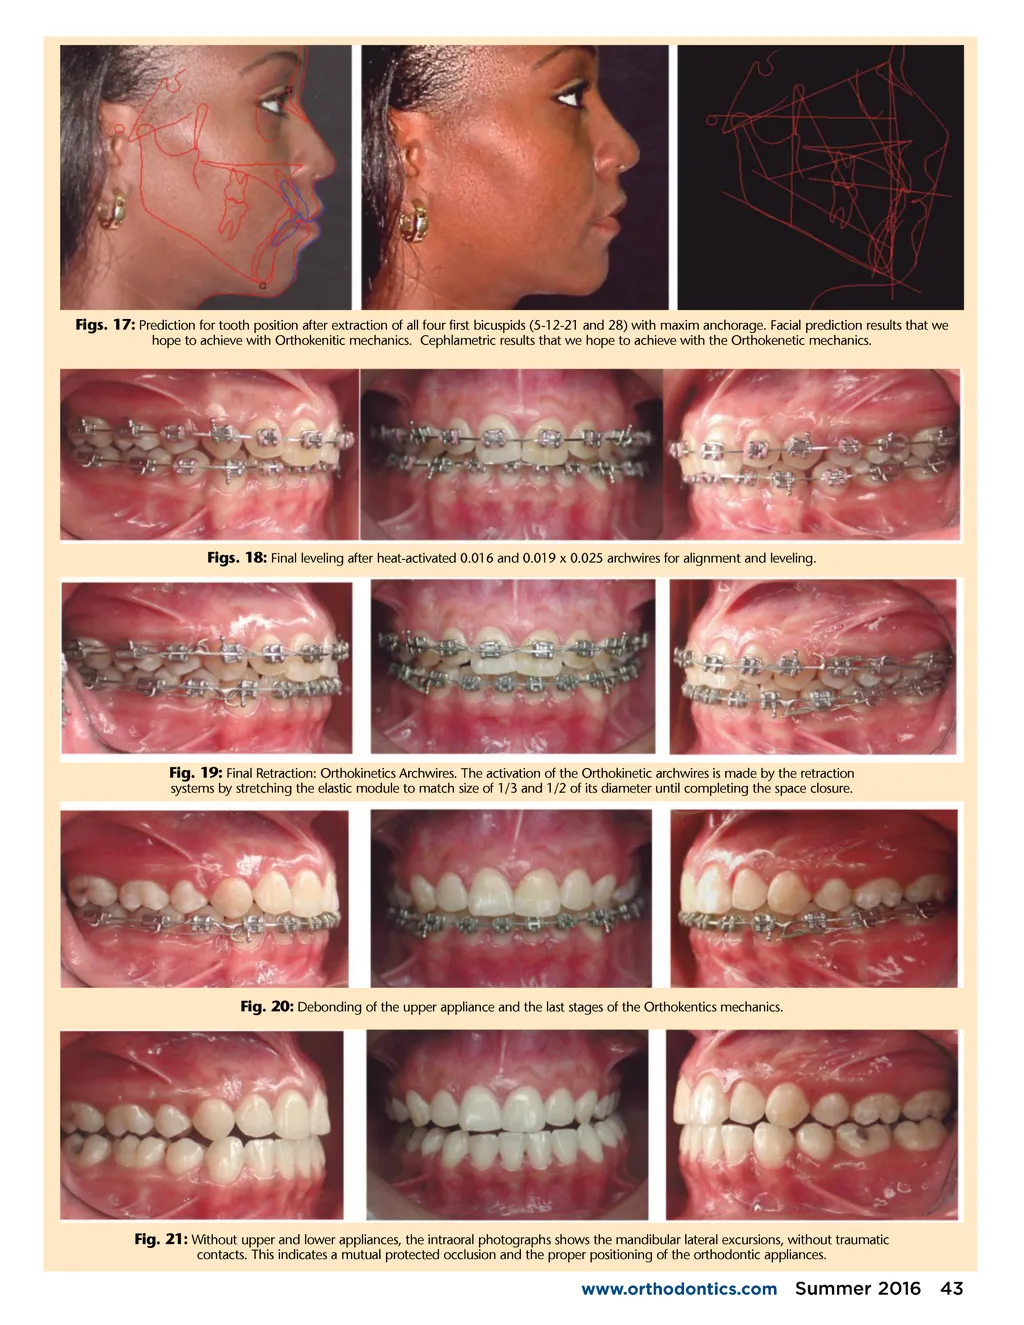

Fig. 12: Initial Cephalogram. Fig. 13: Initial Cephalogram Data. Fig. 14: Antegonial point (Ag) is behind the Ptm Vertical Line. This indicates a Class II mandibular relationship. The Cd point (Condilion in red) indicated the uppermost point of the condyle. Cd is in front of the Tis point (the uppermost point of the glenoid cavity in blue). This indicated condylar anterior displacement. Fig. 15: Initial Orthokinetic Condylar Position Indicator (C.P.I.): It ’ s a function of the Orthokinetor Plus Software, used with cephalometric tracings for the lateral X-ray and panoramic X-ray. In an ideal situation Cd point should be exactly 6.0 mm below Tis point, for proper functioning of the TMJ. This CPI indicates upper and anterior conylardisplacement. the original position in maxim intercuspidation. Green for the predicted right position of the condyles in the TMJ. The graphic representation helps to the re-location of the mandibule before begin the dental movement and to mechanics plan. Fig. 16: Lateral X-ray tracing in blue for 42 Summer 2016 JAOS